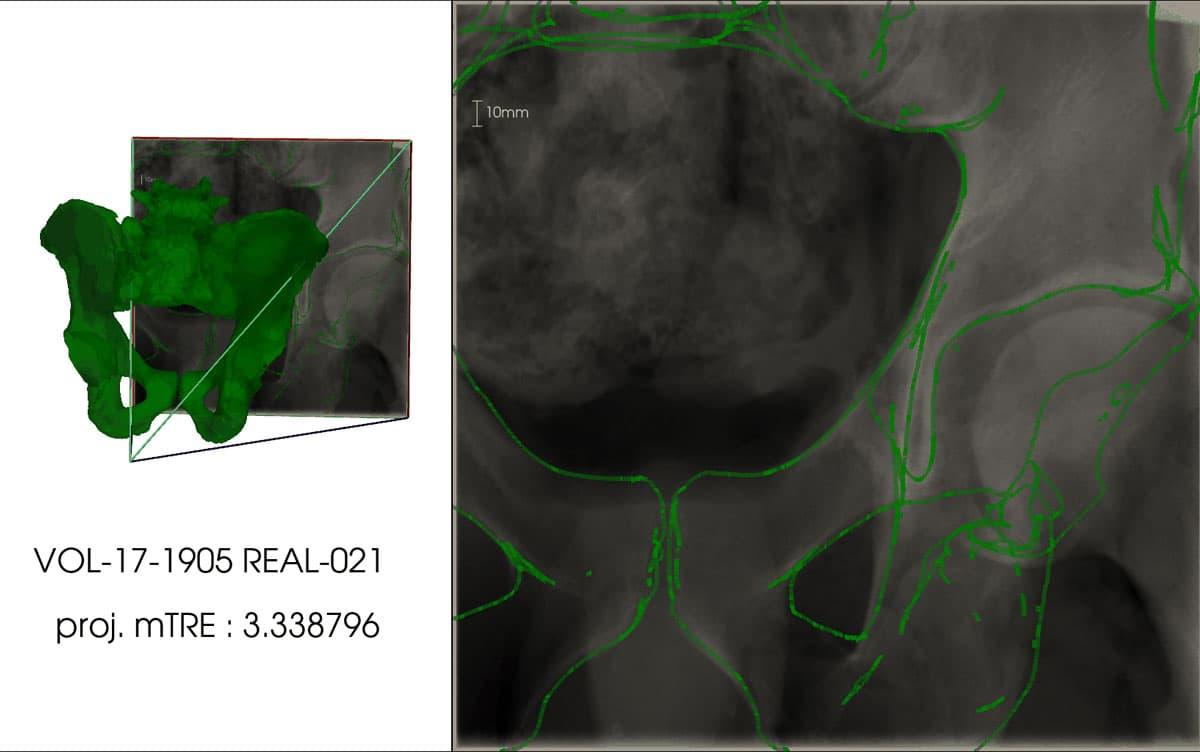

Tsukuba, Japan—The X-ray fluoroscopy machine is a medical device frequently used in orthopedic surgery. Despite its imaging capabilities, physicians heavily rely on their experience and knowledge to align the 3D shape of the target area using the 2D X-ray image. If X-ray images captured during surgery could be superimposed onto a pre-surgical 3D model (CT model) obtained from a CT scan, it would alleviate the cognitive load associated with visualizing the 3D shape from the 2D image, enabling surgeons to focus more on the surgical procedure. To achieve this goal, the superimposition of the X-ray image and CT model data should "work seamlessly, even when focusing on a specific body part (local image)," and the process should to be "fully automated." In this study, researchers met these criteria by employing a convolutional neural network capable of regressing the spatial coordinates of X-ray images. By incorporating correspondence formulation with deep learning techniques, they achieved highly accurate superimposition for local X-ray images.

The efficacy of this technique was verified using a dataset that included CT data and X-ray images of the pelvis. The superimposition of X-ray images and CT data yielded an error of 3.79 mm (with a standard deviation of 1.67 mm) for simulated X-ray images and 9.65 mm (with a standard deviation of 4.07 mm) for actual X-ray images. In the case of actual X-ray images, the superimposition of the X-ray image and CT data produced an error of 9.65 mm (with a standard deviation of 4.07 mm).